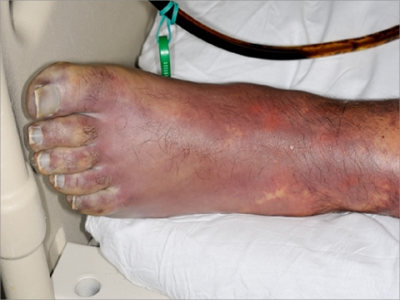

脚部

皮肤发紫

暴发性紫癜脚部皮肤发紫图

暴发性紫癜患者的脚部皮肤颜色全部变为绛紫色,脚趾甲附近皮肤甚至发黑,伴有局部疼痛、发热、乏力等临床表现,可在医生指导下通过药物或者手术进行治疗。